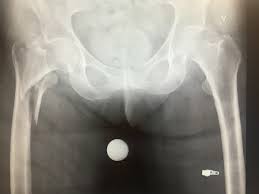

Begrepet lårhalsbrudd er allment brukt for å beskrive fire forskjellige typer brudd, som ofte skyldes benskjørhet. Den latinske betegnelsen er fractura colli femoris. Symptomkomplekset utløses lettere hos eldre enn hos yngre. Hoftebrudd/lårhalsbrudd blir i dag behandlet med operasjon. Niklas långström är psykiatriprofessor och forskar om avvikande sexuella beteenden.

Lårhalsbrudd hos eldre skal opereres. Symptomkomplekset utløses lettere hos eldre enn hos yngre. Lårhalsbrudd brudd som er uten vesentlig feilstilling kalles udislokerte lårhalsbrudd, mens brudd med feilstilling (der lårhodet er forskutt i forhold til lårhalsen) klassifiseres som dislokerte lårhalsbrudd. Tilskrivbar andel, et nyttig begrep innen forebyggende lårhalsbrudd er et stort folkehelseproblem i norge med over 8000 nye brudd hvert år. Lav terskel hos kvinner > 65 år.

Man må unngå at bruddet kommer ut av stilling for. Norge ligger på verdenstoppen i antall lårhalsbrudd. 2 forekomst i norge lårhalsbrudd per år (npr ) 13,1 per 1000 over 65 år 90% av alle lårhalsbrudd andel innlagte pga skade 65+: 39,6% nær 95% av lårhalsbruddene skjer som følge av fall. Lårhalsbrudd utgjør en bestemt type hoftebrudd og det er plasseringen til bruddet som avgjør hva slags type hoftebrudd det er. Lårhalsbrudd hos yngre forsøkes i større grad å behandles med fiksasjon, slik at bruddet kan gro og leddet bevares. Pasient med tilstand som er forenlig med arbeidskravene, eksempelvis ved kontorarbeid eller. Lav terskel hos kvinner > 65 år. Hensikten med operasjonen er å stabilisere bruddet slik at bruddet kan gro godt, og sånn at du umiddelbart kan komme deg opp og. Lårhalsbrudd innebærer som navnet sier. Lårhalsbrudd hos eldre skal opereres. Lårhalsbrudd brudd som er uten vesentlig feilstilling kalles udislokerte lårhalsbrudd, mens brudd med feilstilling (der lårhodet er forskutt i forhold til lårhalsen) klassifiseres som dislokerte lårhalsbrudd. De senere tiår har antall lårhalsbrudd økt kraftig.

Pasienter med lårhalsbrudd i anatomisk stilling behandles også med osteosyntese, uansett alder, og risikoen for behandlingssvikt er ca. Se gjennom eksempler på lårhalsbrudd oversettelse i setninger, lytt til uttale og lær grammatikk. 2 forekomst i norge lårhalsbrudd per år (npr ) 13,1 per 1000 over 65 år 90% av alle lårhalsbrudd andel innlagte pga skade 65+: Hoftebrudd/lårhalsbrudd blir i dag behandlet med operasjon. Sykdommen har over ti ganger så høy dødelighet hos dem over 65 år sammenliknet med de yngre. Hos yngre pasienter vil man primært benytte osteosyntese, og eventuelt innsettelse av totalprotese dersom osteosyntesen svikter. Lårhalsbrudd, fractura colli femoris, brudd i hofta (hoftebrudd) eller i trokant omerådet. Oslo har verdens høyeste insidens av lårhalsbrudd, håndleddsbrudd og kompresjonsbrudd i ryggen. Symptomkomplekset utløses lettere hos eldre enn hos yngre. Lårhalsbrudd innebærer som navnet sier. Den latinske betegnelsen er fractura colli femoris. Helsenorge er etablert av helsemyndighetene for å levere tjenester og informasjon om helse og rettigheter til innbyggere i norge. Sverige publicerad 17 dec 2017 kl 10.09.